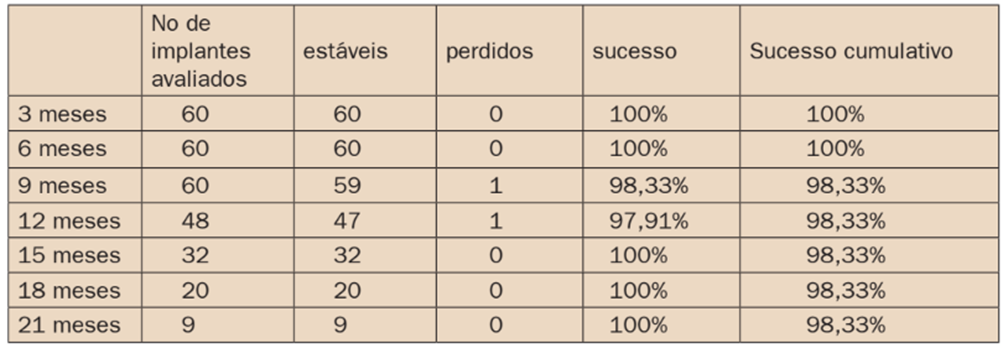

TABELA 3: Avaliação da condição dos implantes nos controles trimestrais, índice de sucesso e sucesso cumulativo dos casos tratados:

Dos 60 implantes instalados, apenas um foi perdido. Este implante apresentou mobilidade excessiva durante o controle de nove meses, sendo removido manualmente sem a necessidade de instrumentos especiais. O caso correspondia a um homem não fumante e o implante estava instalado na região anterior direita, com fixação de 4,0×13, sendo instalado com estabilidade primária de 50 Ncm. A prótese deste caso apresentava uma infraestrutura com barra pré-fabricada de fibra de vidro. O implante perdido foi substituído por outro de 3,5×11, na mesma região, que foi capturado a barra de fibra de vidro e colocado em função imediata. Este implante foi acompanhado junto com os demais por mais seis meses sem apresentar complicações.

Nenhum dos casos apresentou soltura de parafusos protéticos ou dos pilares. Dois pacientes apresentaram queixas fonéticas nos primeiros dois meses, que diminuíram e cessaram após este prazo.

O índice de sobrevivência dos implantes foi de 98,33% em um tempo médio de 14 meses de avaliação. Apesar de um implante perdido, foi possível reaproveitar a prótese sem danos estéticos e funcionais.